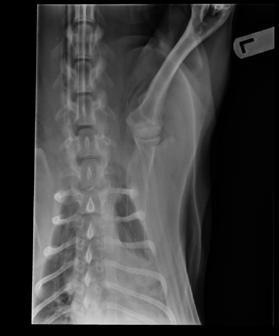

An 8-month-old female desexed Labrador retriever cross presented for a 4–6-week duration of left forelimb lameness.

On clinical exam, there was mild pain on manipulation of both shoulder joints.

Q. What is your radiological diagnosis?